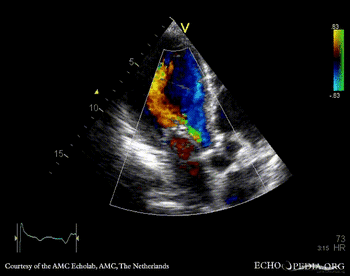

PSAX: thickend aortic valve PLAX: severe aortic and mitral regurgitation